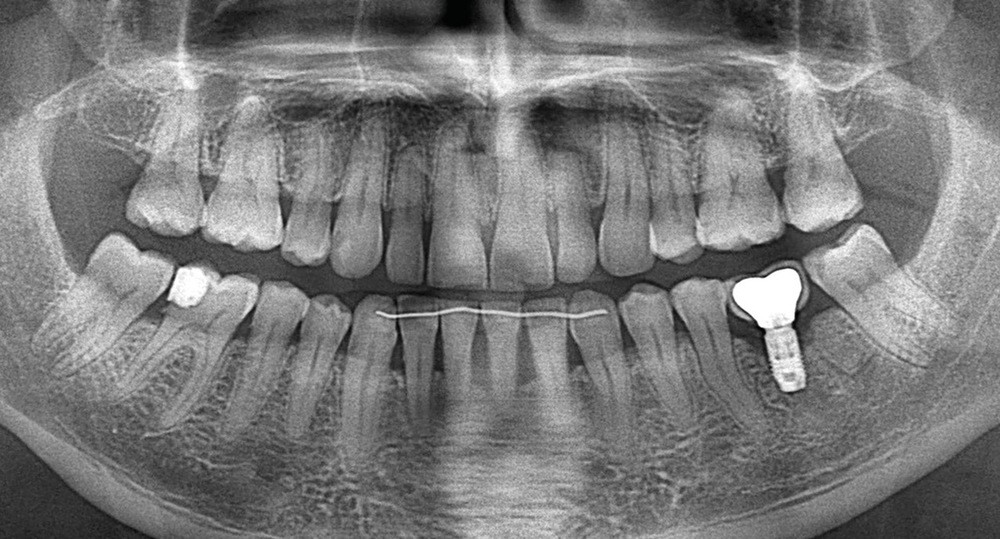

- Avulsion de la 36 et régénération osseuse guidée (ROG) réalisée en 2017 suite à une fracture de la dent et une infection

- Un implant posé en 2018 après la fin du traitement orthodontique

- Couronne d’usage scellée, réalisée par son dentiste

- Péri-implantite diagnostiquée en 2021